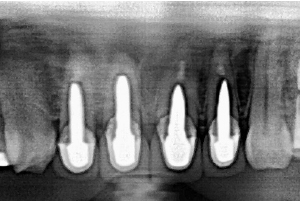

症例

オールセラミック(e-max)

治療前

治療後

治療前のレントゲン

治療後のレントゲン

歯肉退縮により、以前他院で製作されたセラミック冠の審美障害があります。また時々、根元が腫れていたとのこと。前歯4本すべて根管治療を行い、ファイバーコアを入れてからオールセラミック(e-max)で修復しました。術後のレントゲンでは根尖性歯周炎が改善しています。

5ヵ月・20回

¥600,000